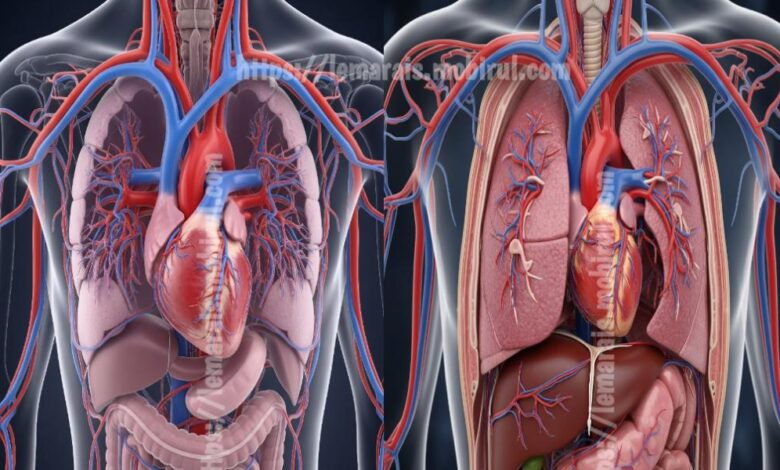

الدكتور المغربي يوسف العزوزي رجل علمي مبدع يخترع جهاز يصفي الدم داخل الأوعية الدموية ليقدم حل طبي يخفف من معاناة المرضى ويقلل الاعتماد على الطرق التقليدية الطويلة في العلاج كما يفتح باب للأمل للمرضى الذين يعانون من مشاكل كلوية حادة وتضيق في الشرايين وتجمع بين التقنية الدقيقة والرحمة في خدمة الحياة

الجهاز الجديد يعمل عبر تقنيات متقدمة تسمح بتنقية الدم مباشرة داخل الأوعية بدون الحاجة لنقل دم خارج الجسم ما يقلل مخاطر العدوى ويحد من الإجهاد على المريض ويعزز سرعة الاستشفاء كما يمهد الطريق لإجراءات قابلة للتحسين في مجالات طبية متعددة مثل الكلى والدماغ والقلب ويتيح متابعة أكثر دقة لحالة المريض من خلال رصد مستمر للمواد المتراكمة وتحسين التوازن الحيوي

تأثير الاختراع على الطب يظهر في تعزيز مفهوم التدخلات القسطرة والداخلية وتطوير أجهزة دقيقة يمكن استخدامها في وحدات العناية المركزة وتطوير بروتوكولات علاجية جديدة كما يشجع الباحثين على الاستثمار في دراسات مقارنة لضمان السلامة والفعالية وتوفير بيانات تثبت جدوى الجهاز وتثري القرارات الطبية وتدعم الأطباء في اختيار أنسب خيارات العلاج للمريضان وتبني تقنيات جديدة في النظم الصحية